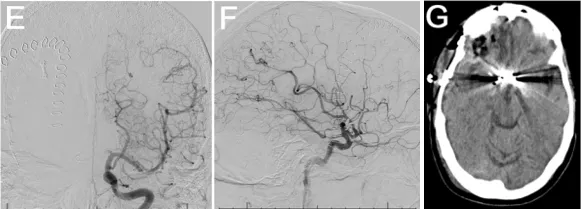

血管造影亦证实存在放射性血管炎。患者随后接受经右侧额部翼点入路开颅术行动脉瘤夹闭术,手术过程顺利。术后DSA显示动脉瘤闭塞有效,无并发症(图1E-G)。

术后脑灌注成像显示一处术前已知的陈旧性脑梗死区域(图1H-J)。患者术后接受随访监测,时长23.9个月。